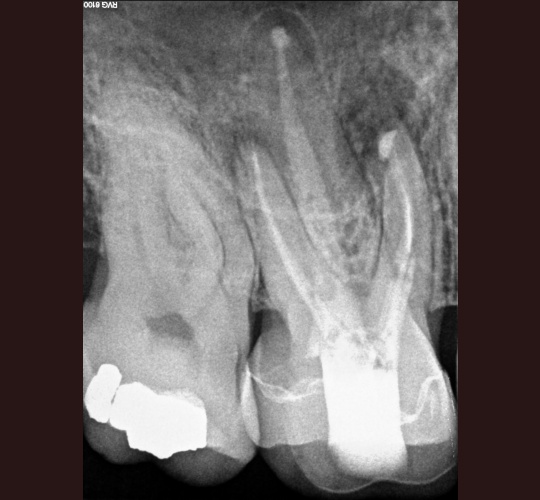

Access Closure: Case #4

When the crown is still intact and in good shape the root canal access opening can be sealed and the crown can be reused. Modern access shape outlines should not overextend and weaken the peri-cervical area. These shapes do not conform to endodontic textbook teachings. These shapes are to be done by qualified microscope using endodontic specialist.

If and only if the doctor feels that sealing your crown can be done to protect your tooth without replacing your crown it may be done in our office by request of your general dentist. If the existing crown is not in excellent shape to prevent leakage into the new root canal your crown may have to be replaced.